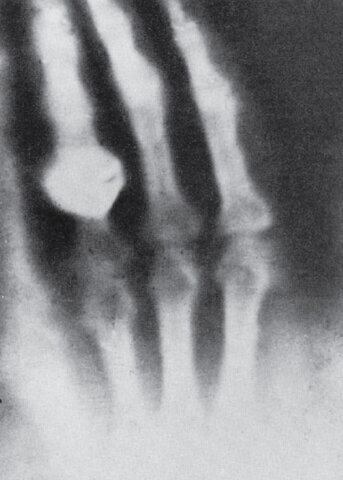

Imagen Radiológica

Esta fue la imagen radiológica de las posibles aplicaciones médicas de los Rayos X y que se realizó a los pocos días de del descubrimiento.